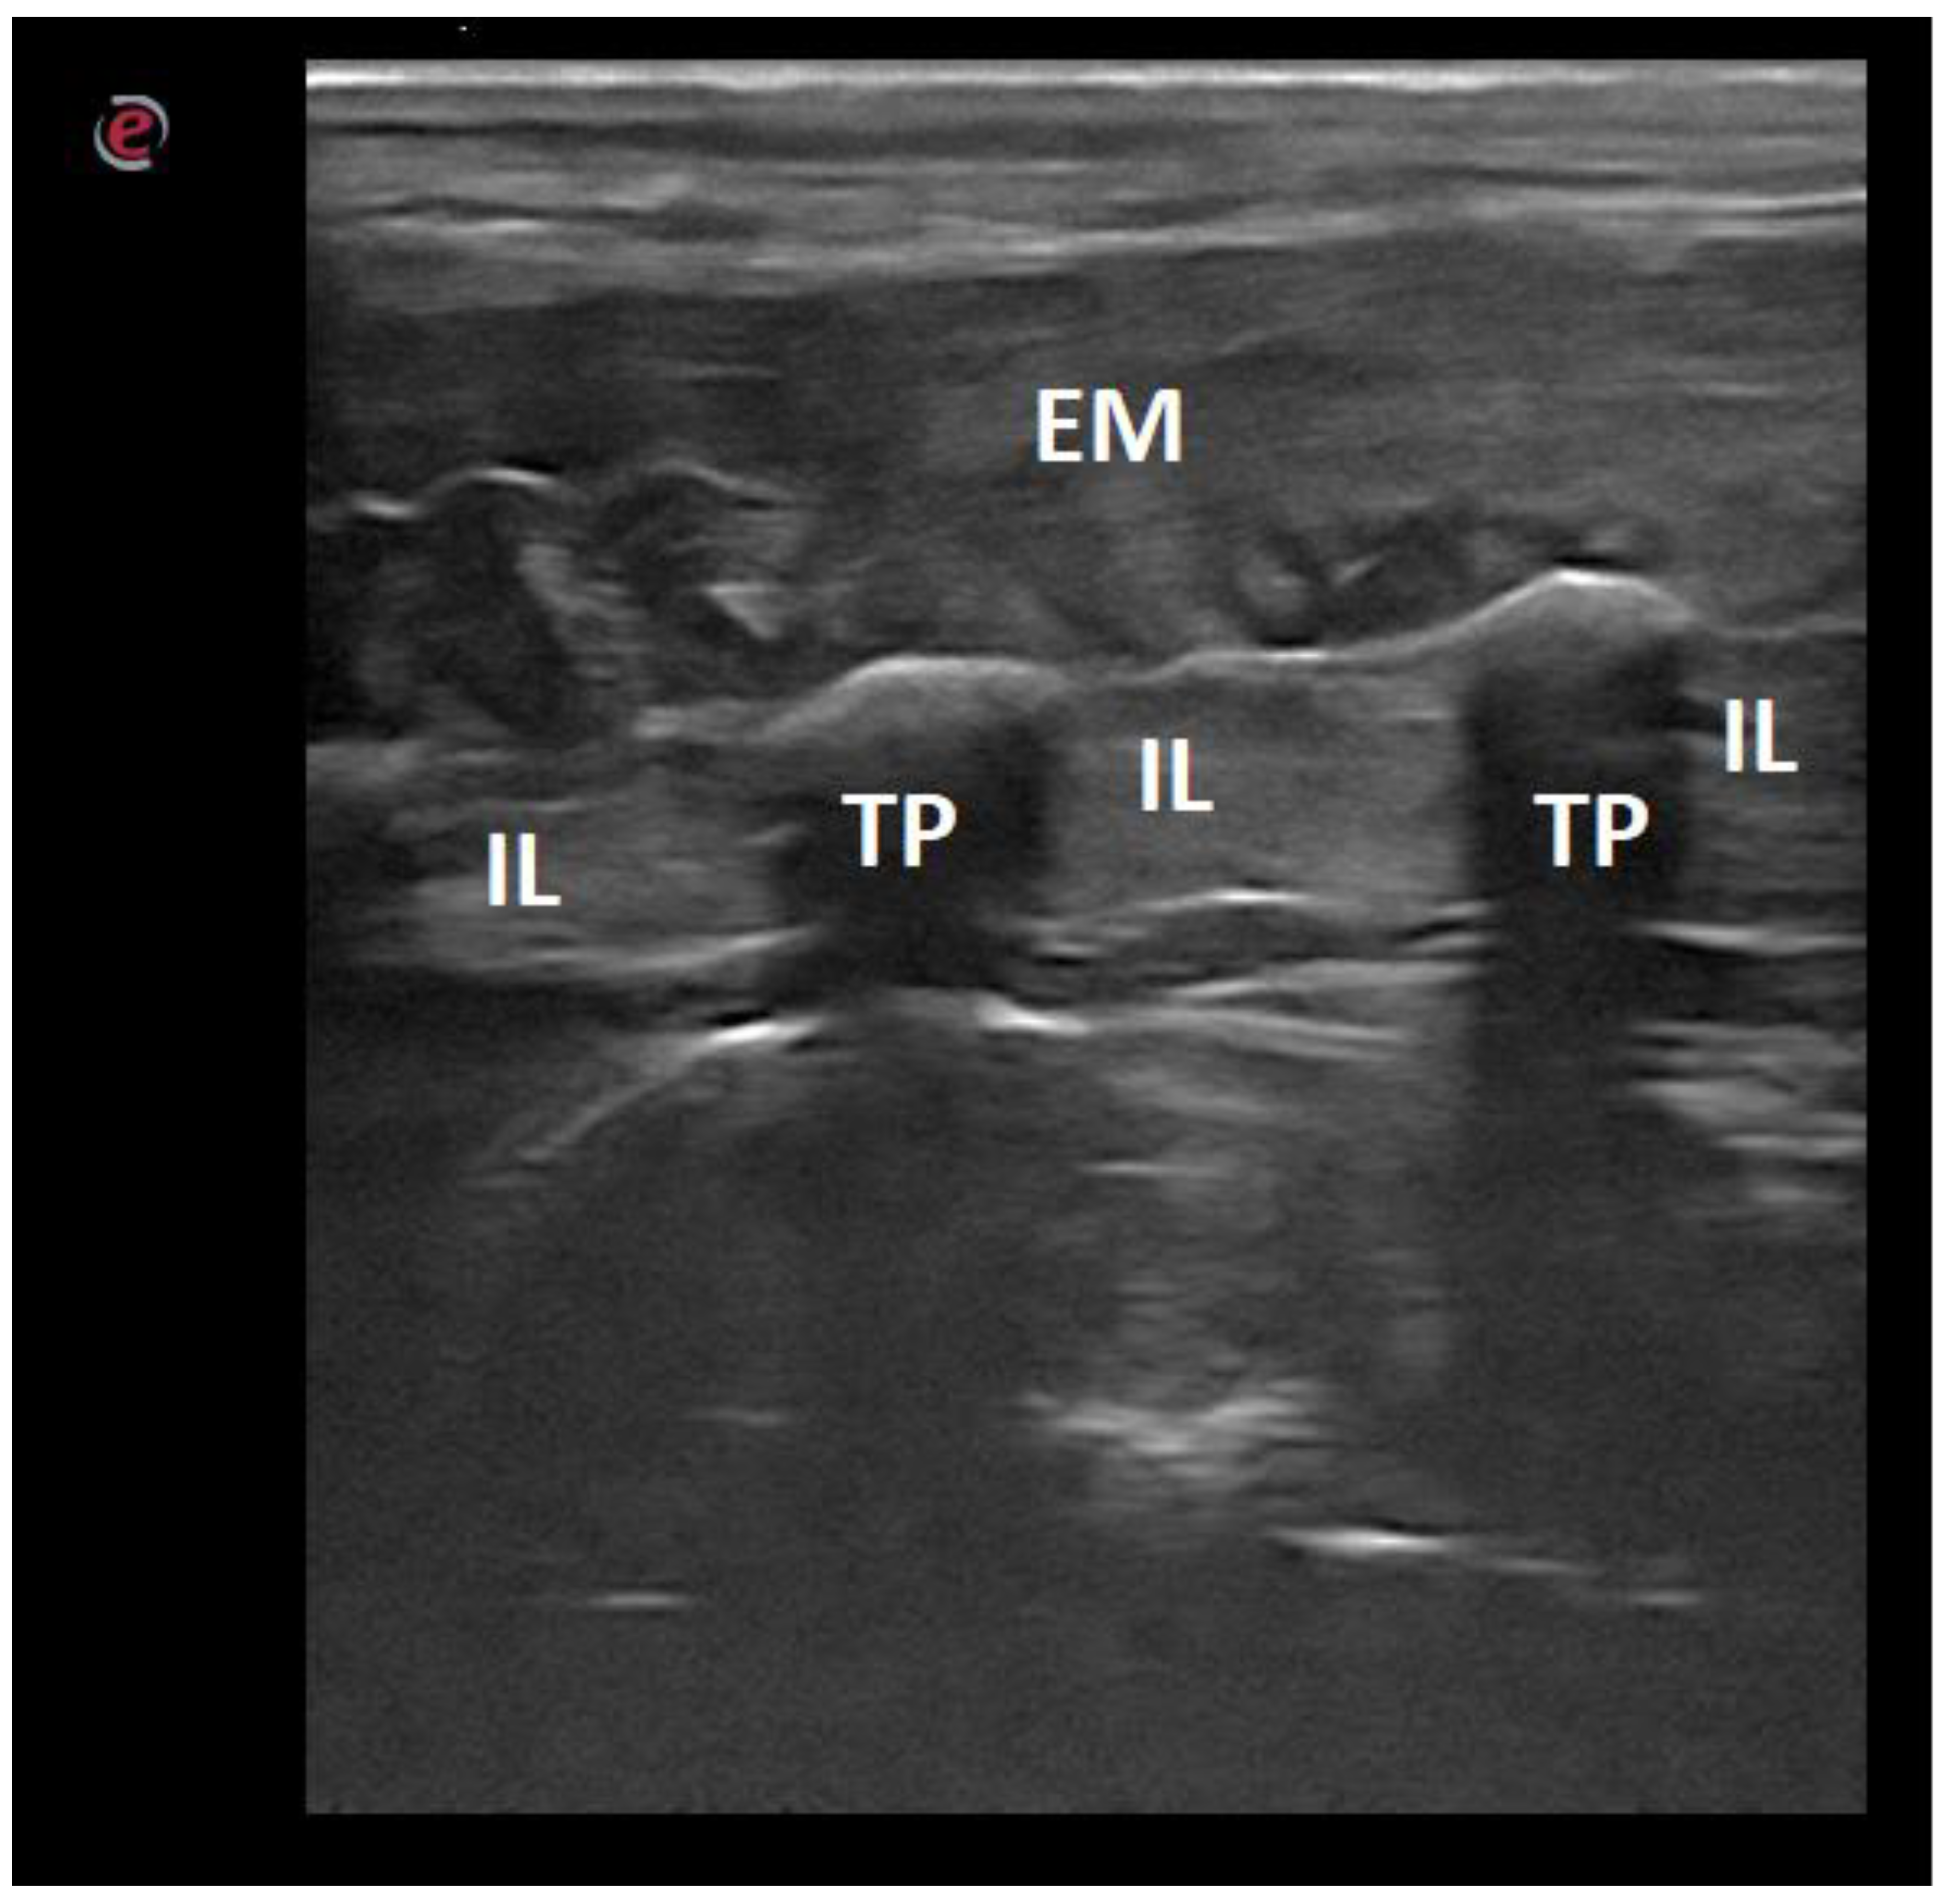

| Intertransverse ligament | 10/43.48 |

| Transverse processes | 15/65.22 |

| Iliocostalis and longissimus muscles | 7/30.43 |